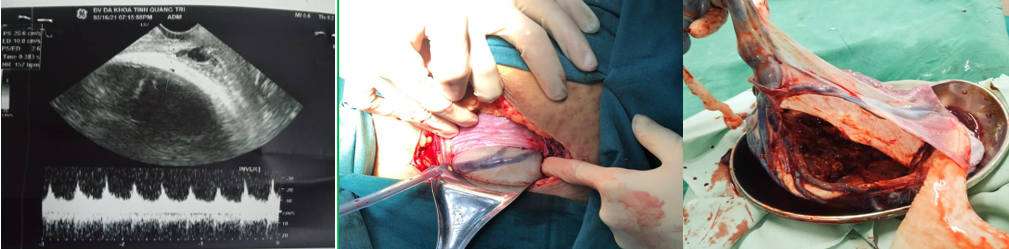

9. BÁO CÁO TRƯỜNG HỢP CHẨN ĐOÁN VÀ XỬ TRÍ THÀNH CÔNG CASE MẠCH MÁU TIỀN ĐẠO TẠI BVĐK TỈNH QUẢNG TRỊThai phụ HTML 28 tuổi mang thai lần 1, 39 tuần. Quá trình khám thai phát hiện dây rốn bám màng mép dưới bánh nhau. Vào viện vì có dấu hiệu chuyển dạ. Ghi nhận lúc vào viện cổ tử cung hở, tử cung gò 1/10 phút. Qua siêu âm ghi nhận 01 thai tương ứng 39 tuần, dây rốn bám màng. Khoa Phụ Sản tiến hành siêu âm Doppler qua đầu dò âm đạo phát hiện mạch máu tiền đạo. Thai phụ được tiến hành mổ lấy thai cấp cứu. Sau mổ đón ra 01 bé trainặng 3800 gr. Trong mổ phát hiện mạch máu tiền đạo. Sau mổ an toàn kiểm tra bánh nhau xác định dây rốn bám màng mạch máu tiền đạo. Sau đó thai phụ được thực hiện da kề da cho em bé. Sau 4 ngày điều trị thai phụ và trẻ sơ sinh xuất viện khỏe mạnh.